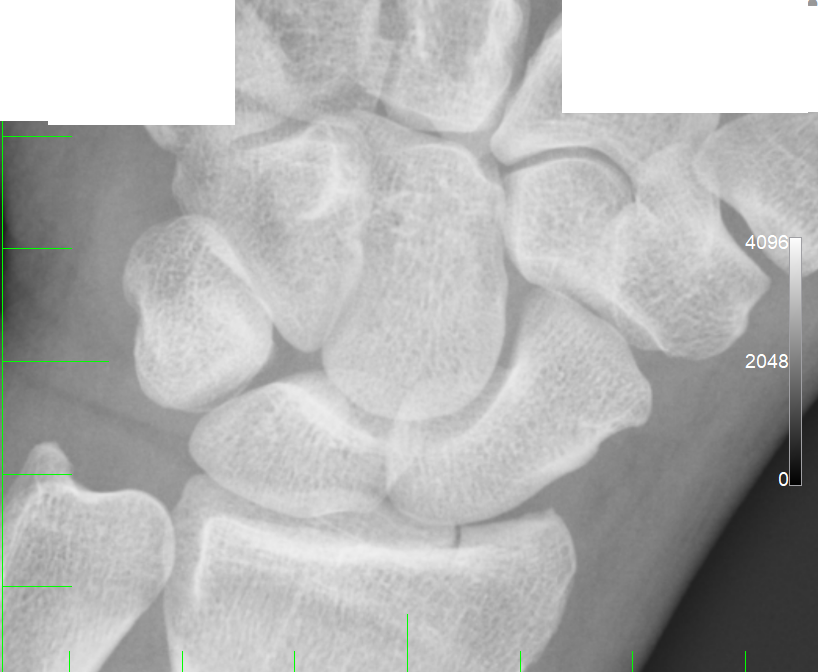

Ieri al pronto soccorso mi hanno diagnosticato frattura composta

articolare dell'epifisi distale del radio, allego immagini,

polso-2.PNG

[ 283.09 KiB | Osservato 1004 volte ]